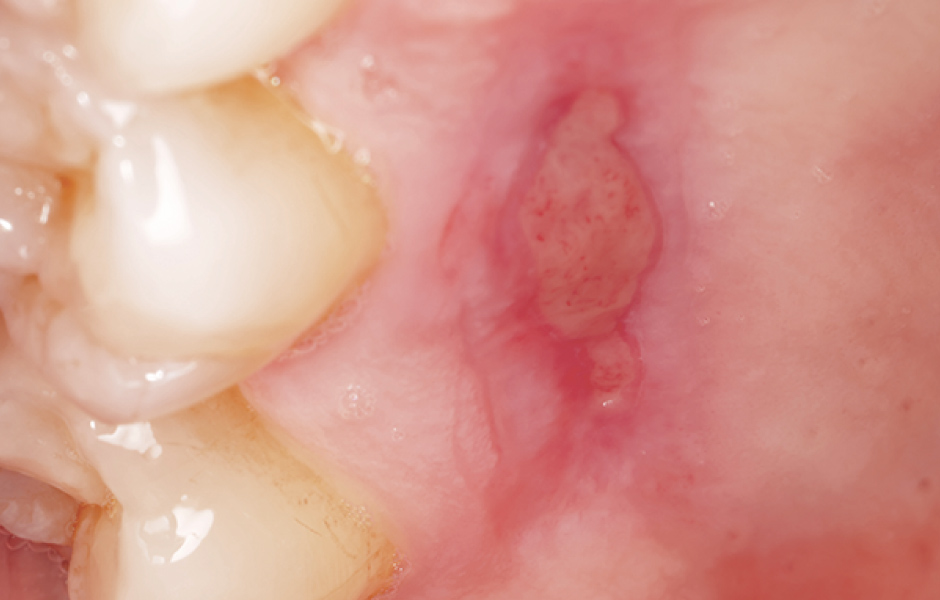

Obr. 2.3: Dárcovské místo po odběru volného epiteliálního štěpu.

Obr. 2.4: Palatální deska z materiálu Elemental stabilizuje krevní sraženinu a urychlí hojení.